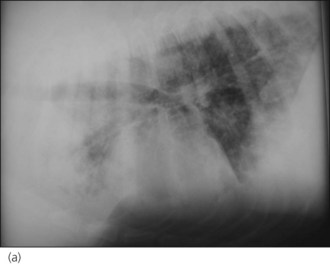

Case management

A diagnosis of severe parasitic pneumonia secondary to Angiostrongylus vasorum infestation was made. As the dog was very amenable, thoracic radiographs were taken following administration of butorphanol (0.2 mg/kg i.v.) with oxygen supplementation throughout and revealed a generalized interstitial to alveolar lung pattern (Figure 33.3). The distribution of the lung changes was considered to be most consistent with parasitic pneumonia.

image image

Figure 33.3 (a) Right lateral and (b) dorsoventral thoracic radiographs from a dog with Angiostrongylus vasorum infection; a generalized interstitial to alveolar lung pattern is present.

Although there are no pathognomic radiographic changes for Angiostrongylus vasorum infection, peripheral and/or multifocal alveolar changes are highly suggestive, especially in a young dog with compatible clinical signs. The distribution of these changes is not a common feature of other causes of alveolar disease (e.g. pulmonary oedema).

Bronchial thickening is also relatively common in dogs with angiostrongylosis.